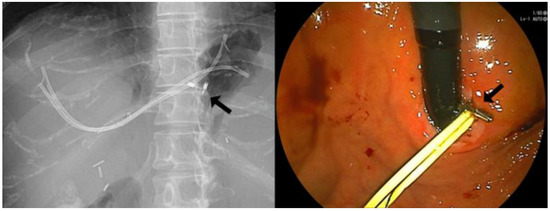

| Dislocation, (%) | 0 | 11 (23) |

| Disappeared | 0 | 5 |

| Migration | 0 | 6 |

| Broken of the FCSEMS, (%) | 0 | 2 (4.2) |

| Placement duration until FCSEMS broken, m | N/A | 7.2/10.3 |